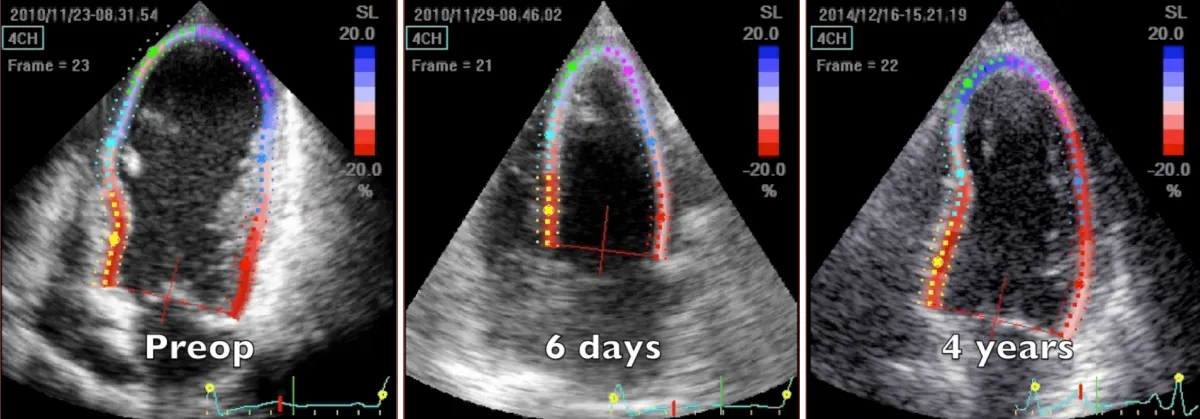

Figure 1: 2D speckle tracking echocardiography 4-chamber systolic frames at three controls, preoperative, 6 days and 4 years after the operation. Note the substantial volume reduction immediately after the operation and the progressive remodeling during time of volume and chamber geometry.

Video 1: Echocardiography apical four-chamber view; comparison between preoperative, 6 days, and 4 years after the operation controls. Note the substantial volume reduction immediately after the operation an d the progressive, positive adjustment during time of volume and chamber geometry, promoted by structural and geometric physiological reconstruction.

Preoperative imaging shows a very large dyskinetic region equal to around half of the ventricular chamber, conditioning a box-shaped ventricle with severely impaired global contraction, wall thickening, and diastolic function. Surgical reconstruction achieved an elliptic chamber with a normal volume and a new apex that were maintained along the years, gradually improving global ejection fraction and diastolic indices (Table 1), showing a positive remodeling induced by the optimised geometrical and functional parameters, left ventricular torsion included. Remote regions show a renewed, increased thickening granted by the better chamber geometry and fibers’ realignment, and the whole left ventricle shows a time-dependent restoration of its functional reserve, preoperatively hidden by the unfavourable functional conditions.

Apical region study (Figure 4 and Video 5) clearly demonstrates an improvement in apical geometry and rotation (from - 4.1 degrees to 4.6 degrees) in the immediate postoperative period induced by the surgically reoriented bundles of fibers. Consequently, left ventricular torsion improved to 7 degrees after the operation, with a reduction to about 4 degrees four years after surgery, due to a new-onset small apical dyskinetic area that reduces counterclockwise rotation to 1.3 degrees. Magnetic resonance short axis views (Figure 3 and Video 4) highlight the physiologically restored left ventricle along its whole length, from the apex to the base. The key surgical steps of this technique are: a) the septal rim of the suture is as long as the patch; b) the lateral rim of the suture shrinks the displaced fibers to a more physiologic orientation, given that it must adapt the dilated lateral wall onto the patch; c) a new apex is rebuilt (elliptic shape); d) a very small “akinetic” patch is used to bring closer the normal myocardium, redirecting fibers in a more physiologic disposition (Video 6).